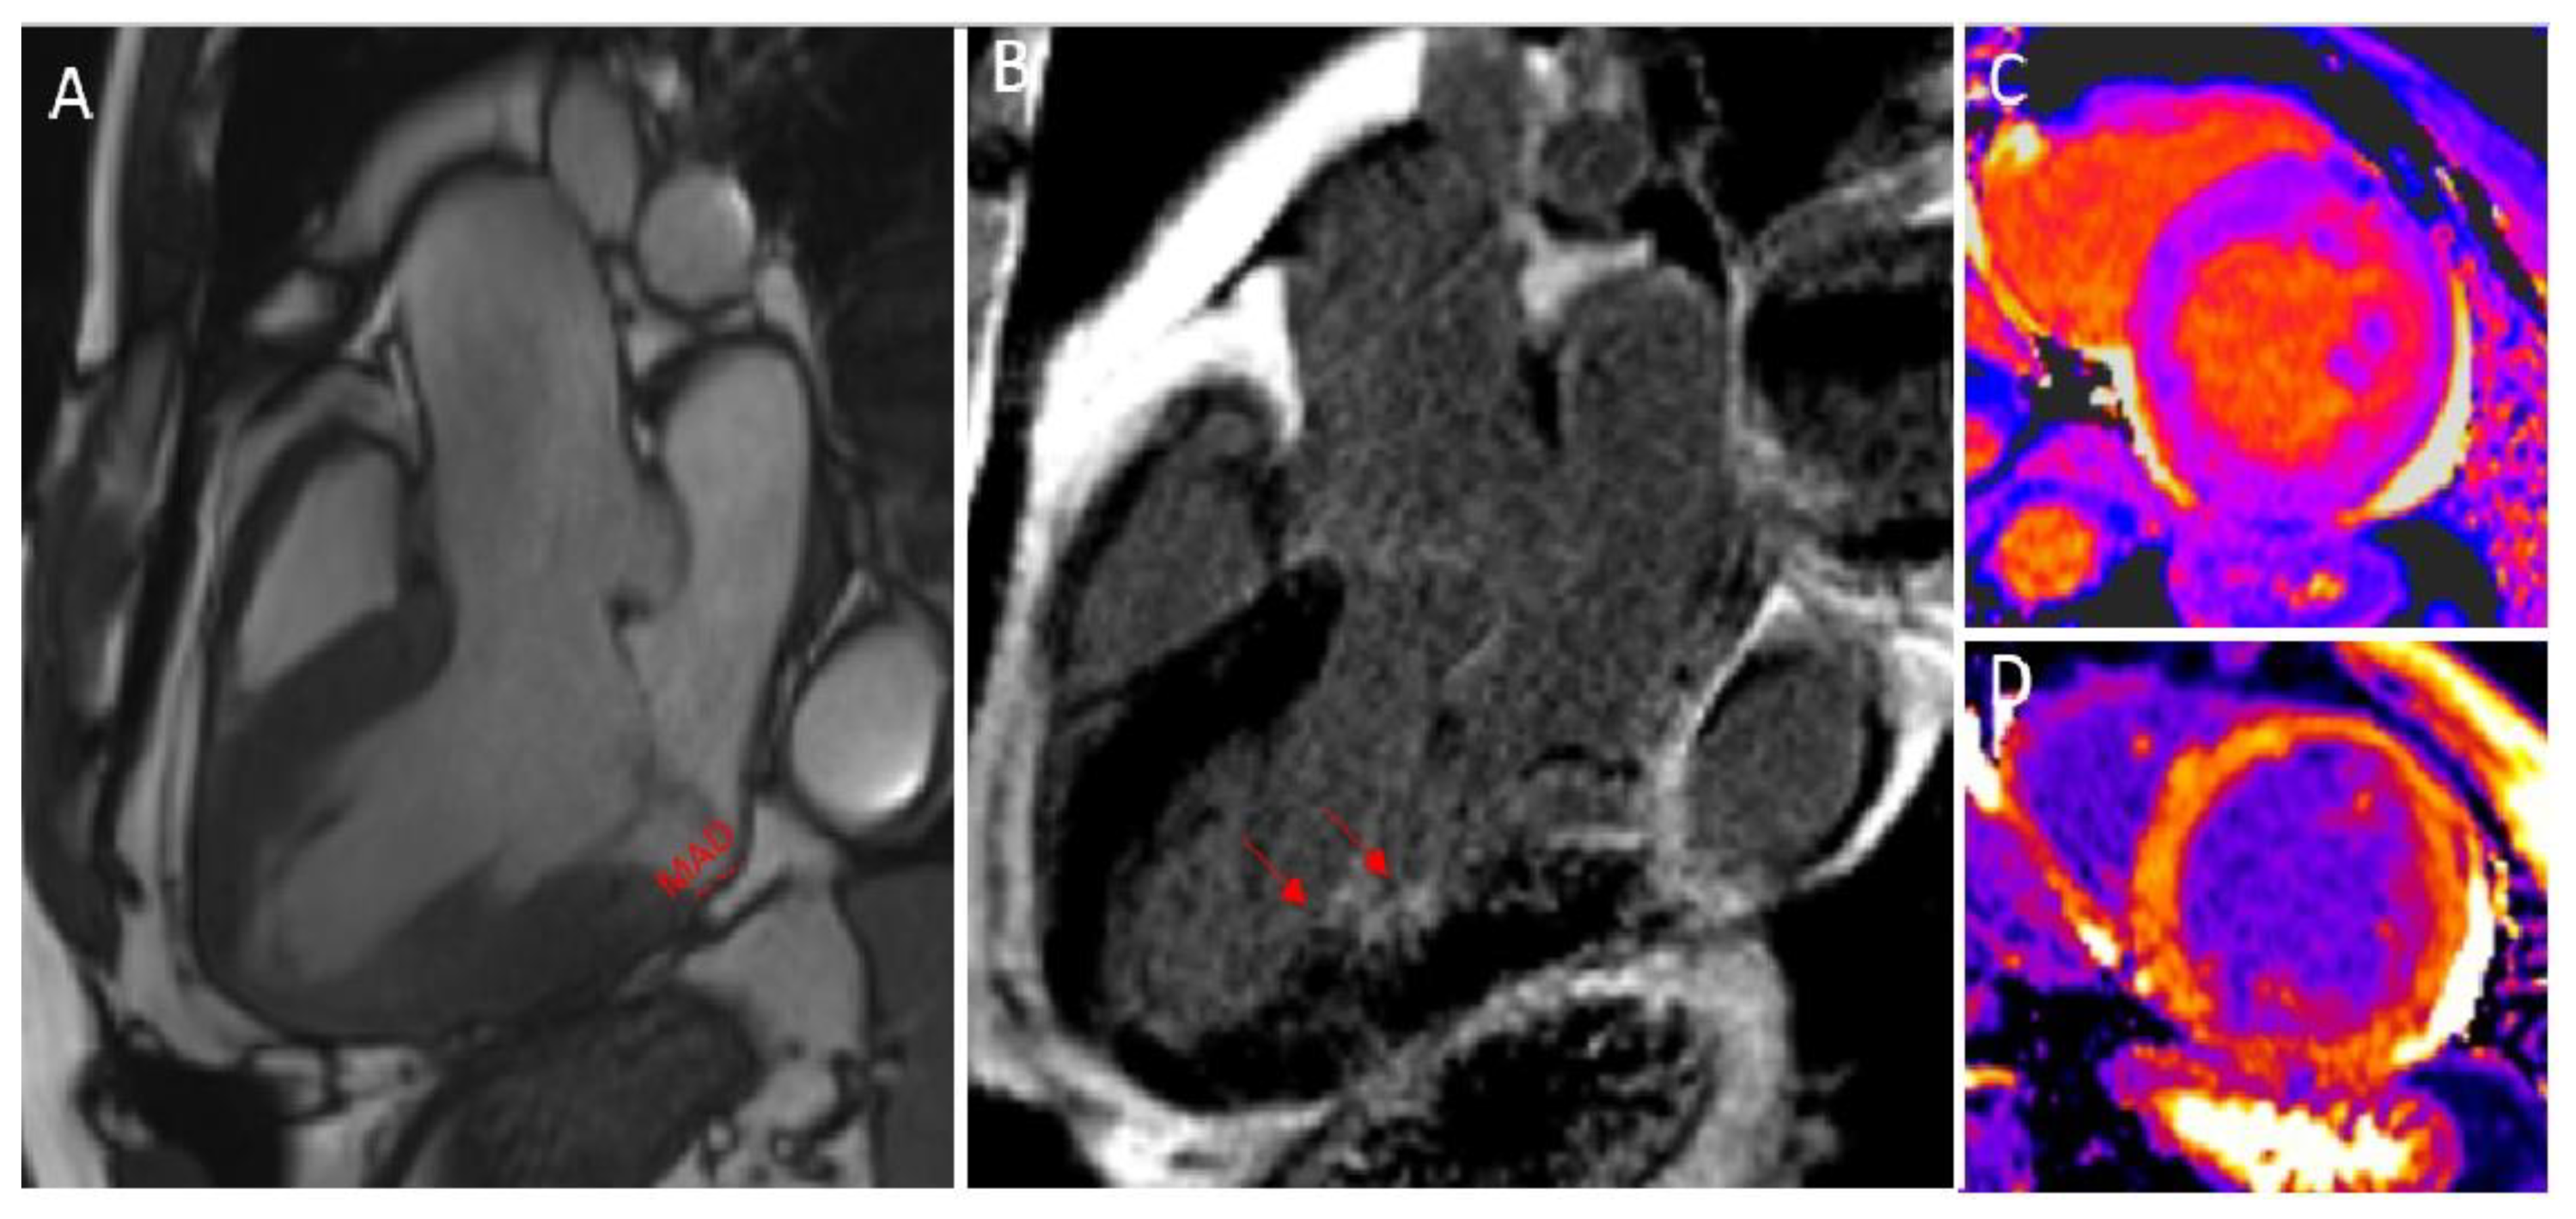

- Pavon, A.; Monney, P.; Schwitter, J. Mitral Valve Prolapse, Arrhythmias, and Sudden Cardiac Death: The Role of Multimodality Imaging to Detect High-Risk Features. Diagnostics 2021, 11, 683. [Google Scholar] [CrossRef] [PubMed]

- Mantegazza, V.; Volpato, V.; Gripari, P.; Ali, S.G.; Fusini, L.; Italiano, G.; Muratori, M.; Pontone, G.; Tamborini, G.; Pepi, M. Multimodality imaging assessment of mitral annular disjunction in mitral valve prolapse. Heart 2020, 107, 25–32. [Google Scholar] [CrossRef] [PubMed]

- Marra, M.P.; Basso, C.; De Lazzari, M.; Rizzo, S.; Cipriani, A.; Giorgi, B.; Lacognata, C.; Rigato, I.; Migliore, F.; Pilichou, K.; et al. Morphofunctional Abnormalities of Mitral Annulus and Arrhythmic Mitral Valve Prolapse. Circ. Cardiovasc. Imaging 2016, 9, e005030. [Google Scholar] [CrossRef]

- Zugwitz, D.; Fung, K.; Aung, N.; Rauseo, E.; McCracken, C.; Cooper, J.; El Messaoudi, S.; Anderson, R.H.; Piechnik, S.K.; Neubauer, S.; et al. Mitral Annular Disjunction Assessed Using CMR Imaging: Insights From the UK Biobank Population Study. JACC Cardiovasc. Imaging 2022, 15, 1856–1866. [Google Scholar] [CrossRef]

- Faletra, F.F.; Leo, L.A.; Paiocchi, V.L.; Schlossbauer, S.A.; Pavon, A.G.; Ho, S.Y.; Maisano, F. Morphology of Mitral Annular Disjunction in Mitral Valve Prolapse. J. Am. Soc. Echocardiogr. 2021, 35, 176–186. [Google Scholar] [CrossRef]